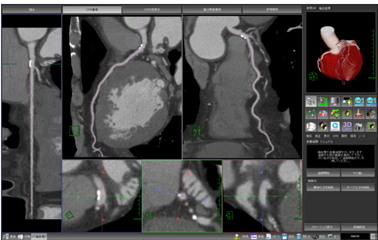

新機能を3つ紹介します。まず1つ目は画面レイアウトです。読影およびレポーティング,画像保存など,目的に応じたレイアウトに改善されました。最適化されたレイアウトでは,1本の血管をあらゆる角度から閲覧でき,詳細な血管の情報を得ることができます。2つ目はVRとCPRとの角度連動機能です(図2)。角度連動機能により,見た目にも直感的にわかりやすい情報提供を可能にしています(図3)。3つ目はレポーティングです。抽出された血管のストレッチCPRや直交断面,VRなどは指定した角度をすべてワンクリックで保存することができます。さらに,より迅速な評価とレポーティングを可能にする冠動脈病変評価チェックシートを搭載しました。

今回CTで使用されている技術は,MRI細血管解析ソフトウェアにも応用され,冠動脈MRAにおいて高精度な心臓抽出を可能にしています。左心耳や肺動脈だけでなく,心臓を取り巻く心嚢水などの高信号成分をボタンのワンクリックで除去できるようになりました。この機能により,MRI心臓データ処理時間を大幅に削減できます。